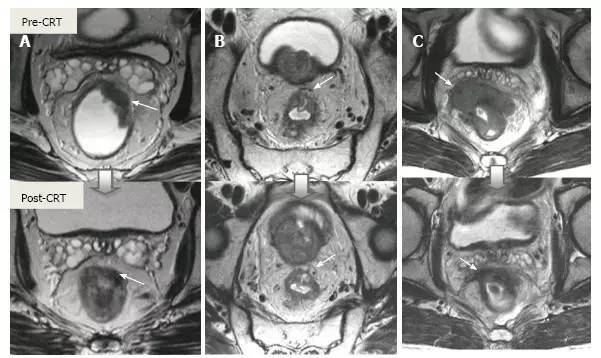

图片

图 17. 新辅助放化疗后肿瘤重新分期。在不同患者的 T2 加权 MR 图像上分别显示(上:治疗前,下:治疗后)。A. 在 ypT0 直肠肿瘤中,治疗后的轴位图像显示正常的两层直肠壁(箭头),对应完全缓解;B. 在 ypT3 直肠肿瘤中,治疗后的轴位图像显示正常的双层直肠壁(箭头)。这是 MR 评估完全缓解的假阴性例子;C. 在 ypT0 直肠肿瘤中,原有肿瘤区域治疗后呈现厚的、纤维化的低信号强度疤痕(箭头)。